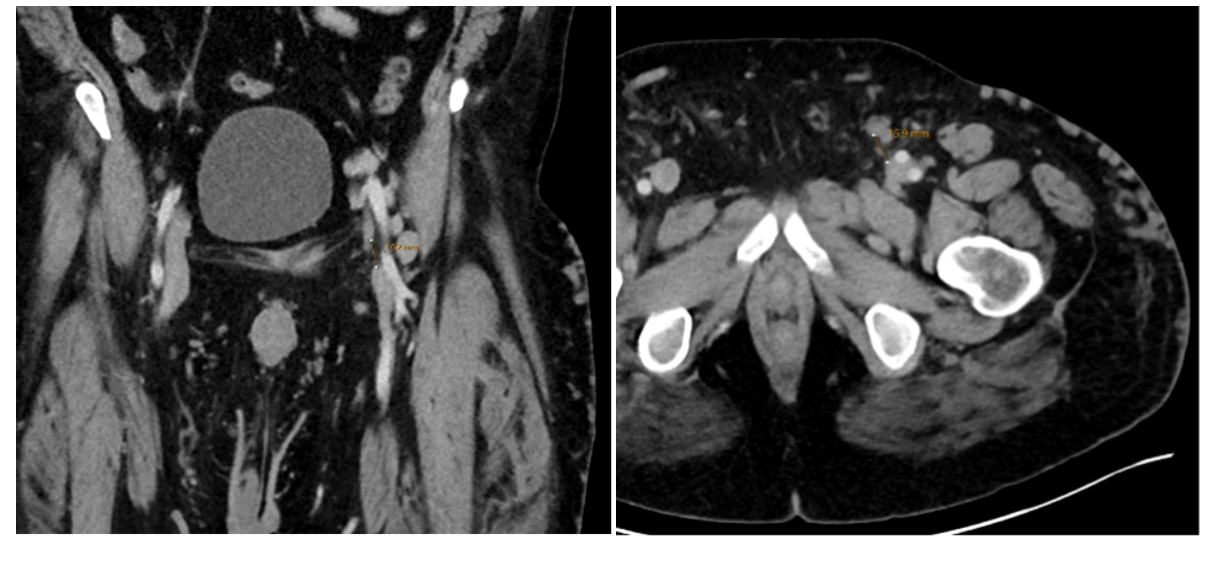

As part of our workup, a computed tomography (CT) venogram was performed. The most important anomaly noted was the absence of a normal left common femoral vein. There were adjacent branches or rudimentary femoral channels terminating near the level of the inguinal ligament, both superior and inferior. Between the closest proximities of these vessels was a roughly 1-cm gap. More proximally, his left iliac veins appeared to be intact (Figures 1 and 2).

Venography was performed in multiple projections. The left groin exposure was utilized for ultrasound assessment of the target vessels. The cephalad channel appeared to parallel the left common femoral artery representing the anatomic location of the normal common femoral vein. The caudal channel was slightly deeper and posterior to the common femoral artery (Figures 3 and 4).